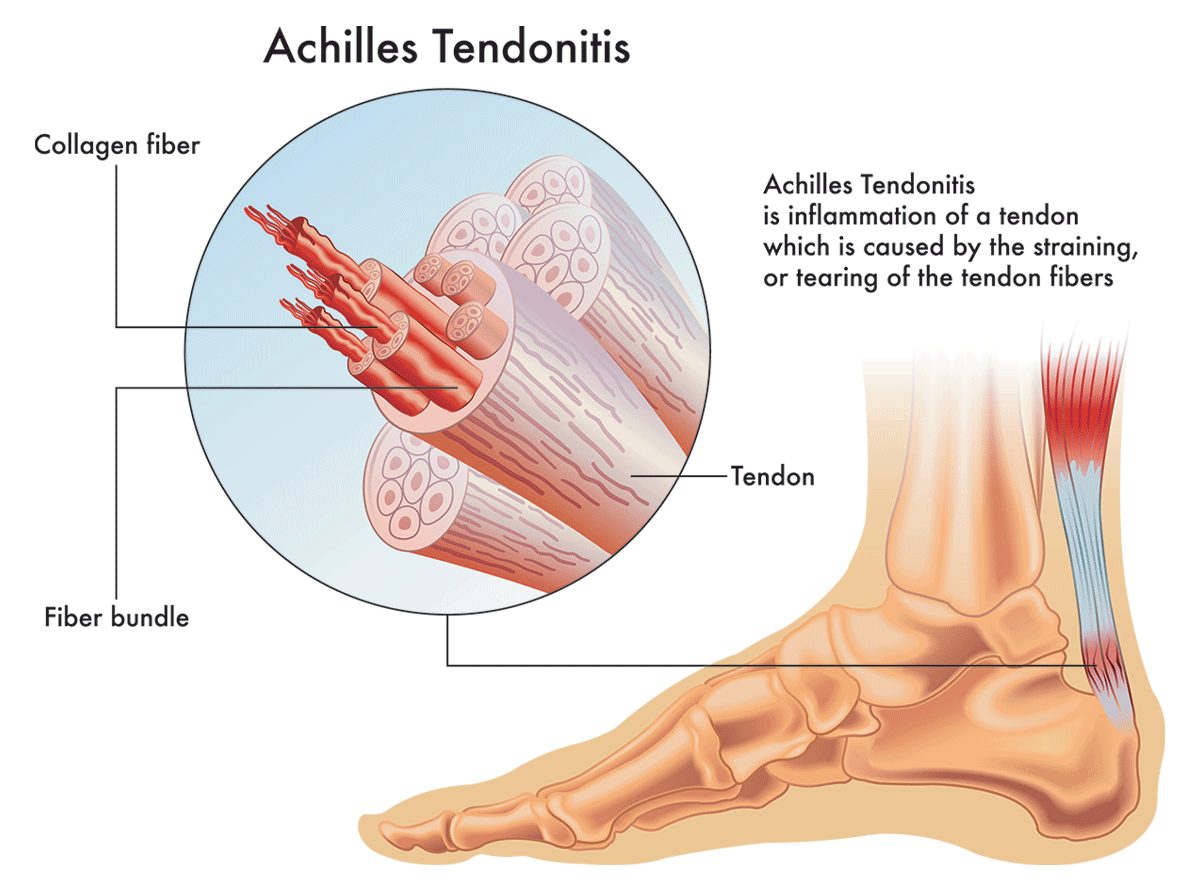

Product Name: Achilles tendon sharp stabbing pain new arrivals

The Signs of Achilles Tendinitis Sydney Heel Pain new arrivals, Heel Pain Causes Treatment and Prevention new arrivals, Sharp Pain in the Achilles Tendon Causes Best Treatment new arrivals, Achilles tendinitis Information Mount Sinai New York new arrivals, Achilles Tendonitis Treatment in Gilbert Scottsdale Chandler Mesa Phoenix new arrivals, Achilles Tendon Tear Kenneth Bramlett MD new arrivals, Know the Symptoms of Achilles Tendonitis Tendinopathy Gait Happens new arrivals, What Causes Pain In Back Of Heel Tendon Injury Symptoms new arrivals, Achilles Tendon Pain and Injury Treatment in Chatswood new arrivals, Achilles Tendon Pain Causes Treatment Sydney Heel Pain new arrivals, Achilles Tendinopathy Kintec Footwear Orthotics new arrivals, Fast Effective Relief for Achilles Tendon Pain Manchester Burnley new arrivals, Common Conditions Causing Heel Pain new arrivals, Insertional Achilles Tendinopathy Sussex Foot And Ankle Clinic new arrivals, Achilles Tendinitis Symptoms Treatment new arrivals, Achilles tendon sharp clearance pain new arrivals, Severs Disease Sever s Disease Treatment Sydney new arrivals, Sharp Pain in Foot Causes Symptoms and Treatments Modern Foot Ankle new arrivals, Achilles Tendonosis and Tendonitis Achilles Tendonosis and Tendonitis Chiropractors for Chandler Sun Lakes and Ocotillo Arizona new arrivals, Heel Pain Bunbury Foot Ankle Surgeon new arrivals, Achilles Tendon Pain Causes Treatments Prevention new arrivals, What Can Cause Sharp Stabbing Foot Pain new arrivals, Protecting Your Achilles Heel From Injury Dr Gordon Slater new arrivals, Pain In The Back Of The Heel What Could It Mean new arrivals, Plantar fasciitis Altru Health System new arrivals, Spink Physiotherapy Achilles tendon pain Achilles tendon pain often occurs due to overuse sudden increased intensity of physical activity poor footwear tight calf muscles improper warm up inadequate r... new arrivals, Pain at the back of the heel How to figure out what s causing it and what to do about it new arrivals, 4 Heel Pain Symptoms to Take Seriously Chicagoland Foot and Ankle Board Certified Foot and Ankle Specialists and Surgeons new arrivals, Sharp Pain in the Achilles Tendon Causes Best Treatment new arrivals, Ankle Pain Causes Treatment Northeast Spine and Sports Medicine new arrivals, Achilles Tendinitis Ankle Pain Foot Injury new arrivals, Achilles Tendonitis Causes Symptoms Signs Gleneagles Hospital new arrivals, Pain at the back of the heel How to figure out what s causing it and what to do about it new arrivals, Achilles Tendonitis Vs Plantar Fasciitis Which Do I Have new arrivals, Achilles Tendon Pain Symptoms Causes Treatment Exercises new arrivals.

Achilles tendon sharp stabbing pain new arrivals